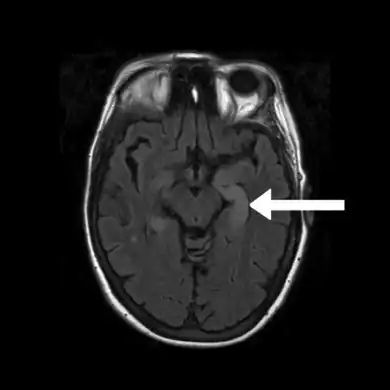

.png.webp) Image of limbic encephalitis (and positive NMDAR antibodies in the CSF)- increased signal intensity is seen in the bilateral medial temporal lobes and hippocampi.

Image of limbic encephalitis (and positive NMDAR antibodies in the CSF)- increased signal intensity is seen in the bilateral medial temporal lobes and hippocampi. FLAIR MRI-Indicates bright signal from medial temporal lobe consistent with limbic encephalitis arrow

FLAIR MRI-Indicates bright signal from medial temporal lobe consistent with limbic encephalitis arrow

Neuroimaging

Brain MRI is the mainstay of initial investigation pointing to limbic lobe pathology revealing increased T2 signal involving one or both temporal lobes in most cases.[22][14]

Serial MRI in LE starts as an acute disease with uni- or bilateral swollen temporomesial structures that are hyperintense on fluid attenuation inversion recovery and T2-weighted sequences. Swelling and hyperintensity may persist over months to years, but in most cases progressive temporomesial atrophy develops.[23]